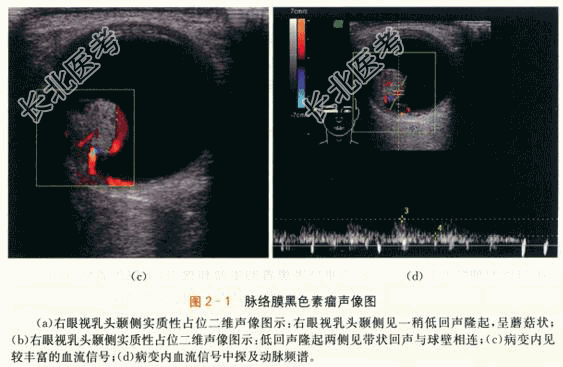

- [材料题] 患者,男性,52岁,因“右眼视力逐渐下降半年.眼前黑影伴视物变形1周”就诊。体格检查:患者视野检查示蓝色视野缺损大于红色视野缺损。特殊检查:眼底检查示右眼玻璃体混浊。颞侧可见脉络膜实性隆起,呈棕褐色,表面有出血。隆起物周边视网膜呈青灰色隆起。影像资料如下: